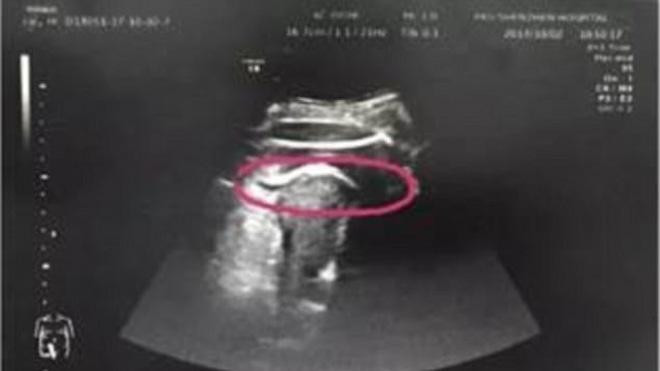

Hình ảnh siêu âm cho thấy tử cung của sản phụ bị thai nhi đạp rách. (Ảnh: Daily Mail)

Kết quả siêu âm cho thấy, tử cung bị rách như các bác sỹ phỏng đoán và nguyên nhân do thai nhi 35 tuần tuổi đạp vỡ. Đứa trẻ thậm chí còn thò chân sang khoang bụng khiến đùi bị mắc kẹt ở thành tử cung.